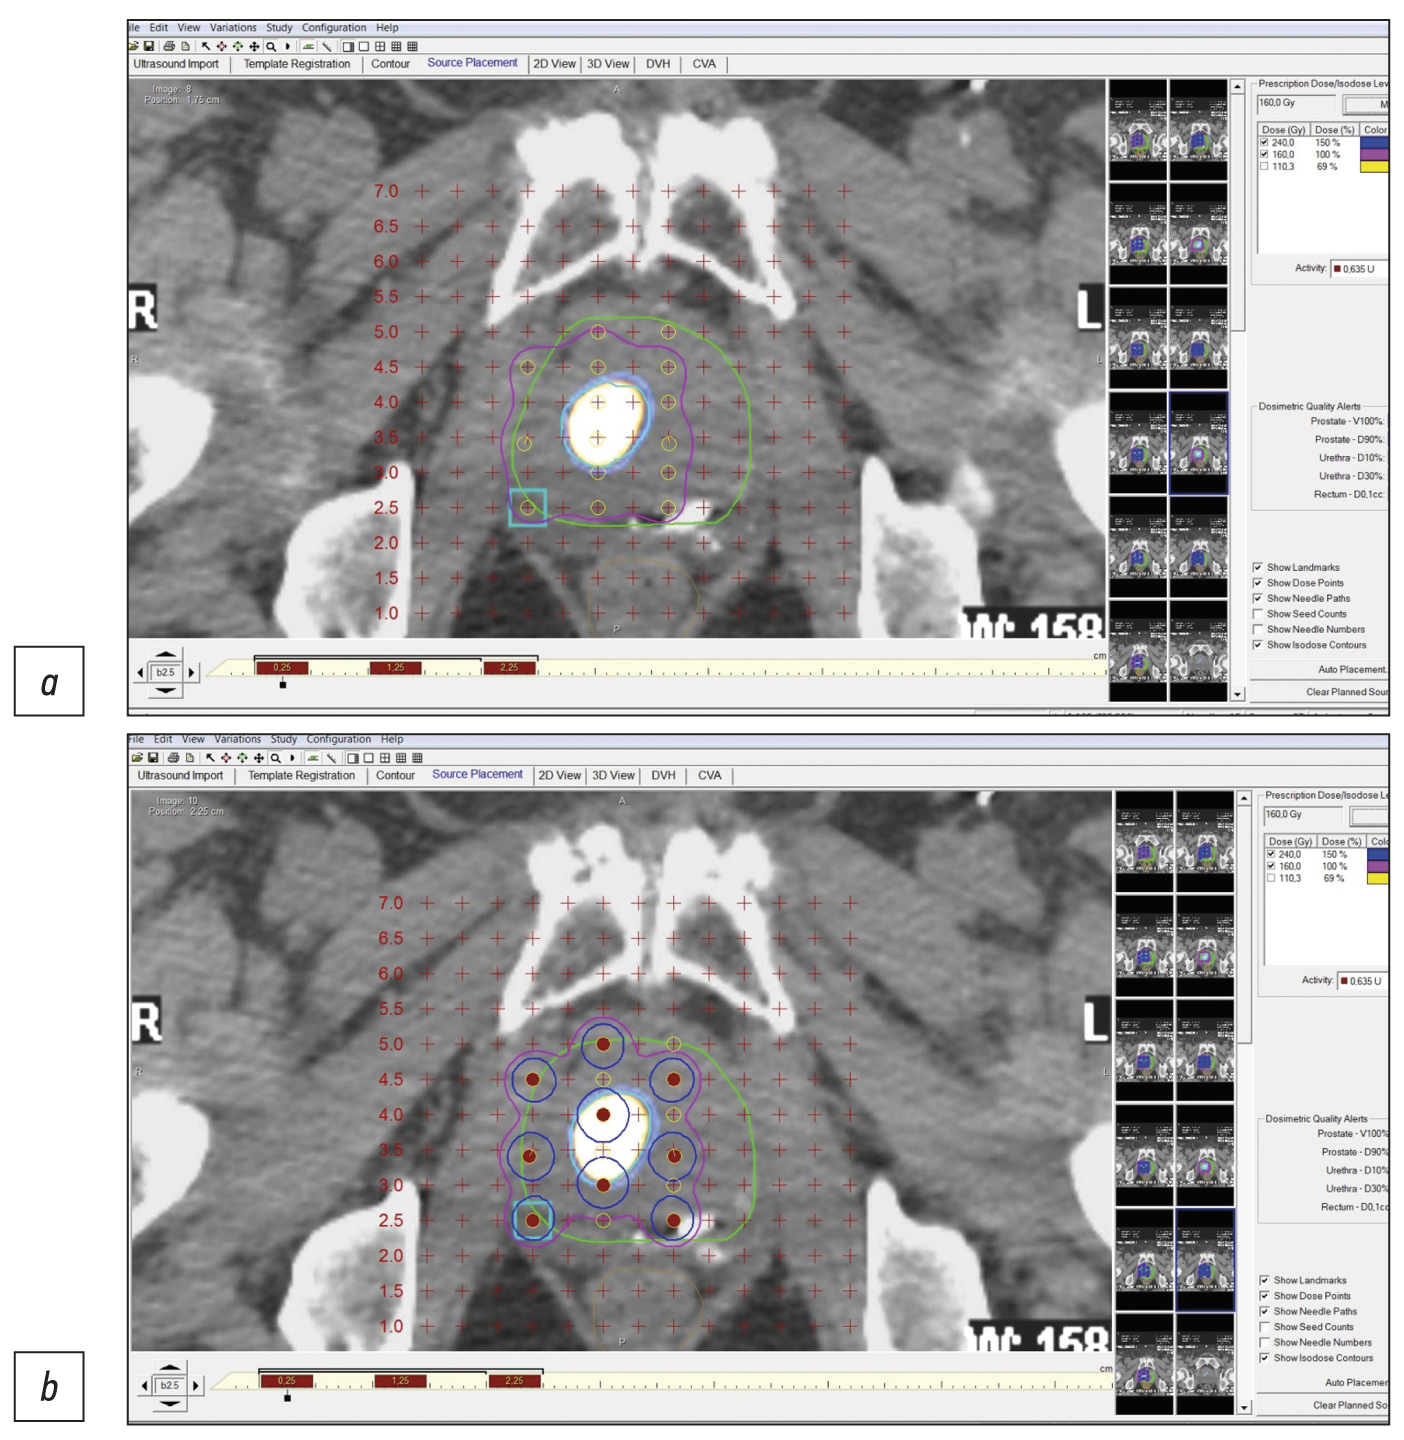

Case report 6

Patient M., 65 years old, was diagnosed with benign prostatic hyperplasia. Due to an increased PSA level of 4.5 ng/mL, a US-guided multifocal biopsy was performed with no histological evidence of cancer. A repeat biopsy was performed 3 months later and revealed no malignant tumor. SPECT/CT with 99mTc-HYNIC-PSMA revealed a site of RP accumulation in the prostate tissue (Figure 7). A CT-guided targeted biopsy was performed, and the following diagnosis was morphologically confirmed: adenocarcinoma, Gleason 7 (4 + 3). When planning low-dose brachytherapy using 125I microsources, SPECT/CT data were entered into the dosimetry planning system. On October 4, 2020, the focal implantation of 125I microsources was performed under a CT guide using pararectal access based on data on local isotope accumulation in the prostate tissue. The follow-up examination (January 2023) showed a 0.11-ng/mL PSA level.

Fig. 7. Patient M., 65 years old, SPECT/CT with 99mTc-HYNIC-PSMA: Site of radiopharmaceutical accumulation in the transition zone (at the border of the middle third and the base) of the left prostate lobe.